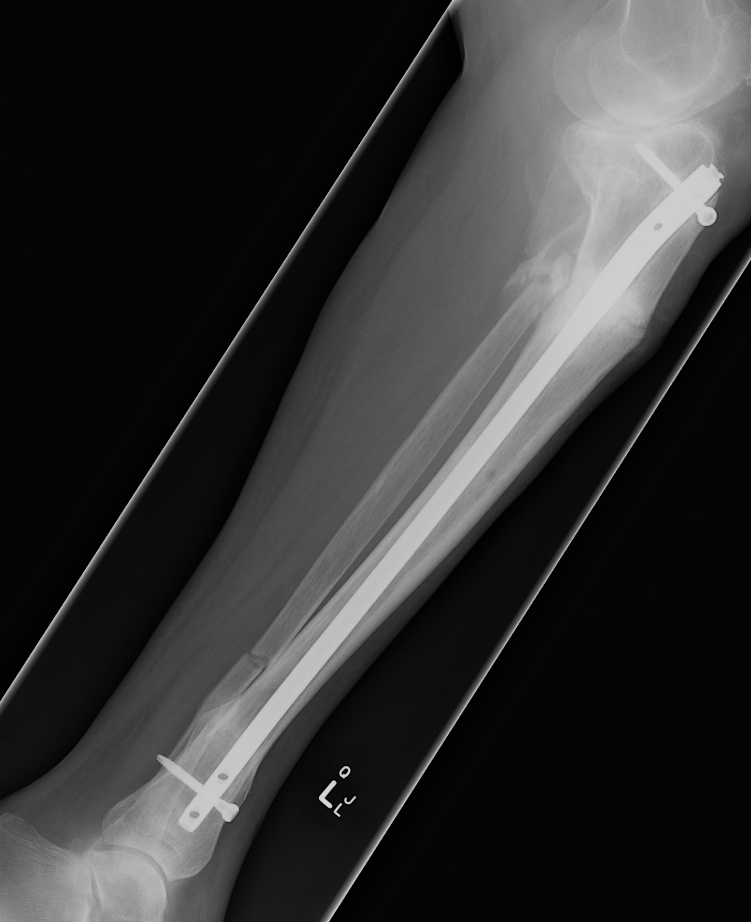

Proximal metaphyseal tibial fracture

Risk of delayed valgus deformity

Acceptable reduction

- varus / valgus < 5o

- anterior / posterior < 5o

- rotation 5o

- shortening 10 mm

Poor remodelling potential

- valgus

- apex posterior angulation / recurvatum

- rotational alignment does not remodel

- shortening / in 2-10 year old average overgrowth is only 5mm